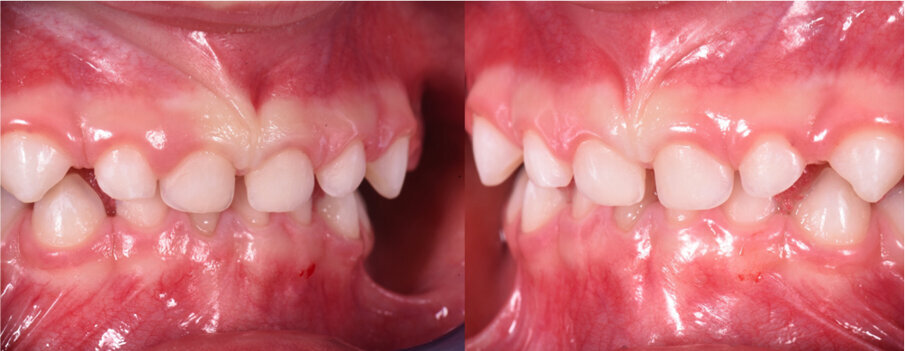

Caso 2 Paziente di anni 4, malocclusione dentale di III Classe, morso crociato monolaterale dx. La paziente viene trattata con dispositivo Amcop TC 2, il quale indossato tutte le notti e 1 ora di pomeriggio in 8 mesi risolve la malocclusione ripristinando il corretto rapporto occlusale; durante la terapia si riscontra un netto miglioramento della respirazione nasale e quindi il ripristino delle normali funzioni respiratorie. Il dispositivo, nei mesi successivi, viene indossato dalla paziente solo la notte per stabilizzare il caso e per guidare la crescita nel miglior modo possibile; all’età di 6 anni la paziente viene sottoposta a check-up ortodontico completo e quindi a panoramica e teleradiografia per poter analizzare anche la previsione di crescita e stabilire un eventuale step elastodontico (Figg. 15-23).

Fig. 15

Fig. 16

Fig. 17

Fig. 18

Fig. 19

Fig. 20

Fig. 21

Fig. 22

Fig. 23